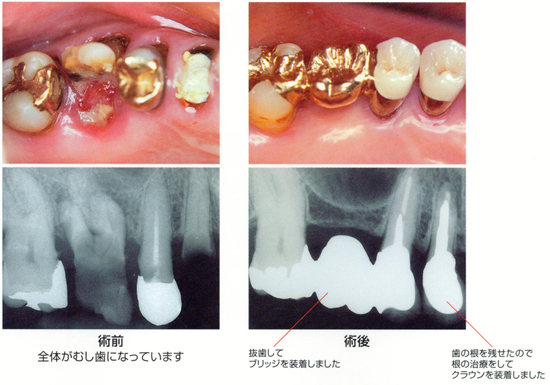

C4(シーフォー)

歯全体が、虫歯に侵されています。

歯の根の先に膿がたまったり、歯の周りにも病気の影響が及び、歯を残すのが難しくなります。